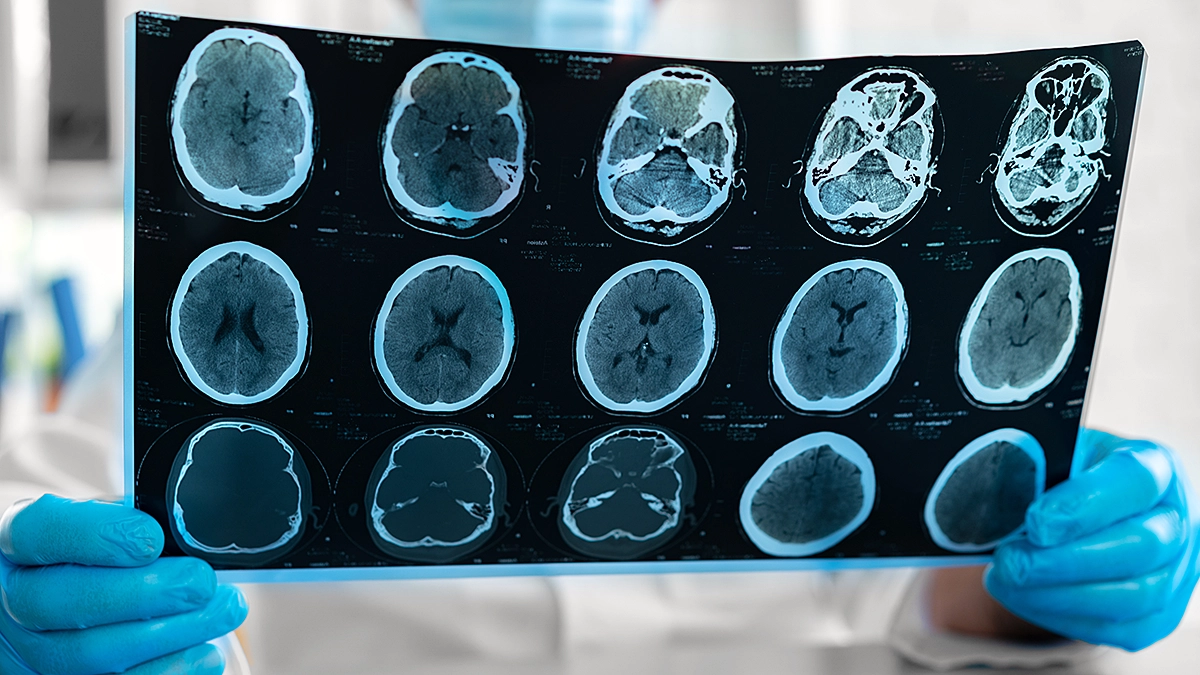

In the shadow of the acute challenges presented by Traumatic Brain Injuries (TBIs) lies a far more insidious risk, one that extends its reach far into the future of affected individuals. Emerging research has illuminated a startling connection between moderate to severe cases of TBI and a dramatic increase in the risk of dementia — with individuals facing an average 150% heightened risk compared to those without TBI. Furthermore, the specter of a decreased lifespan, by an astonishing average of 9 years, looms large for those who have suffered from significant brain injuries. These revelations underscore the urgent need for a paradigm shift in approaching TBI diagnosis, treatment, and long-term management.

The complexities of TBI cannot be overstated. Beyond the initial impact and immediate aftermath lies a cascade of potential long-term effects that can profoundly alter an individual’s health trajectory. The linkage between TBI and significantly elevated risks of developing dementia highlights the brain’s vulnerability to neurodegenerative processes triggered by injury. This increased risk underscores the critical importance of acute care and long-term monitoring and intervention strategies to mitigate these risks.

Recognizing the profound impact that moderate to severe TBI can have on an individual’s future, the practice emphasizes a comprehensive approach to care. This includes the immediate and thorough evaluation of any head injury and a sustained, long-term management plan tailored to each patient’s unique needs. Such plans are critical in monitoring for and addressing early signs of cognitive decline and other neurodegenerative symptoms, potentially offering a pathway to mitigate the increased risk of dementia and other long-term health issues.